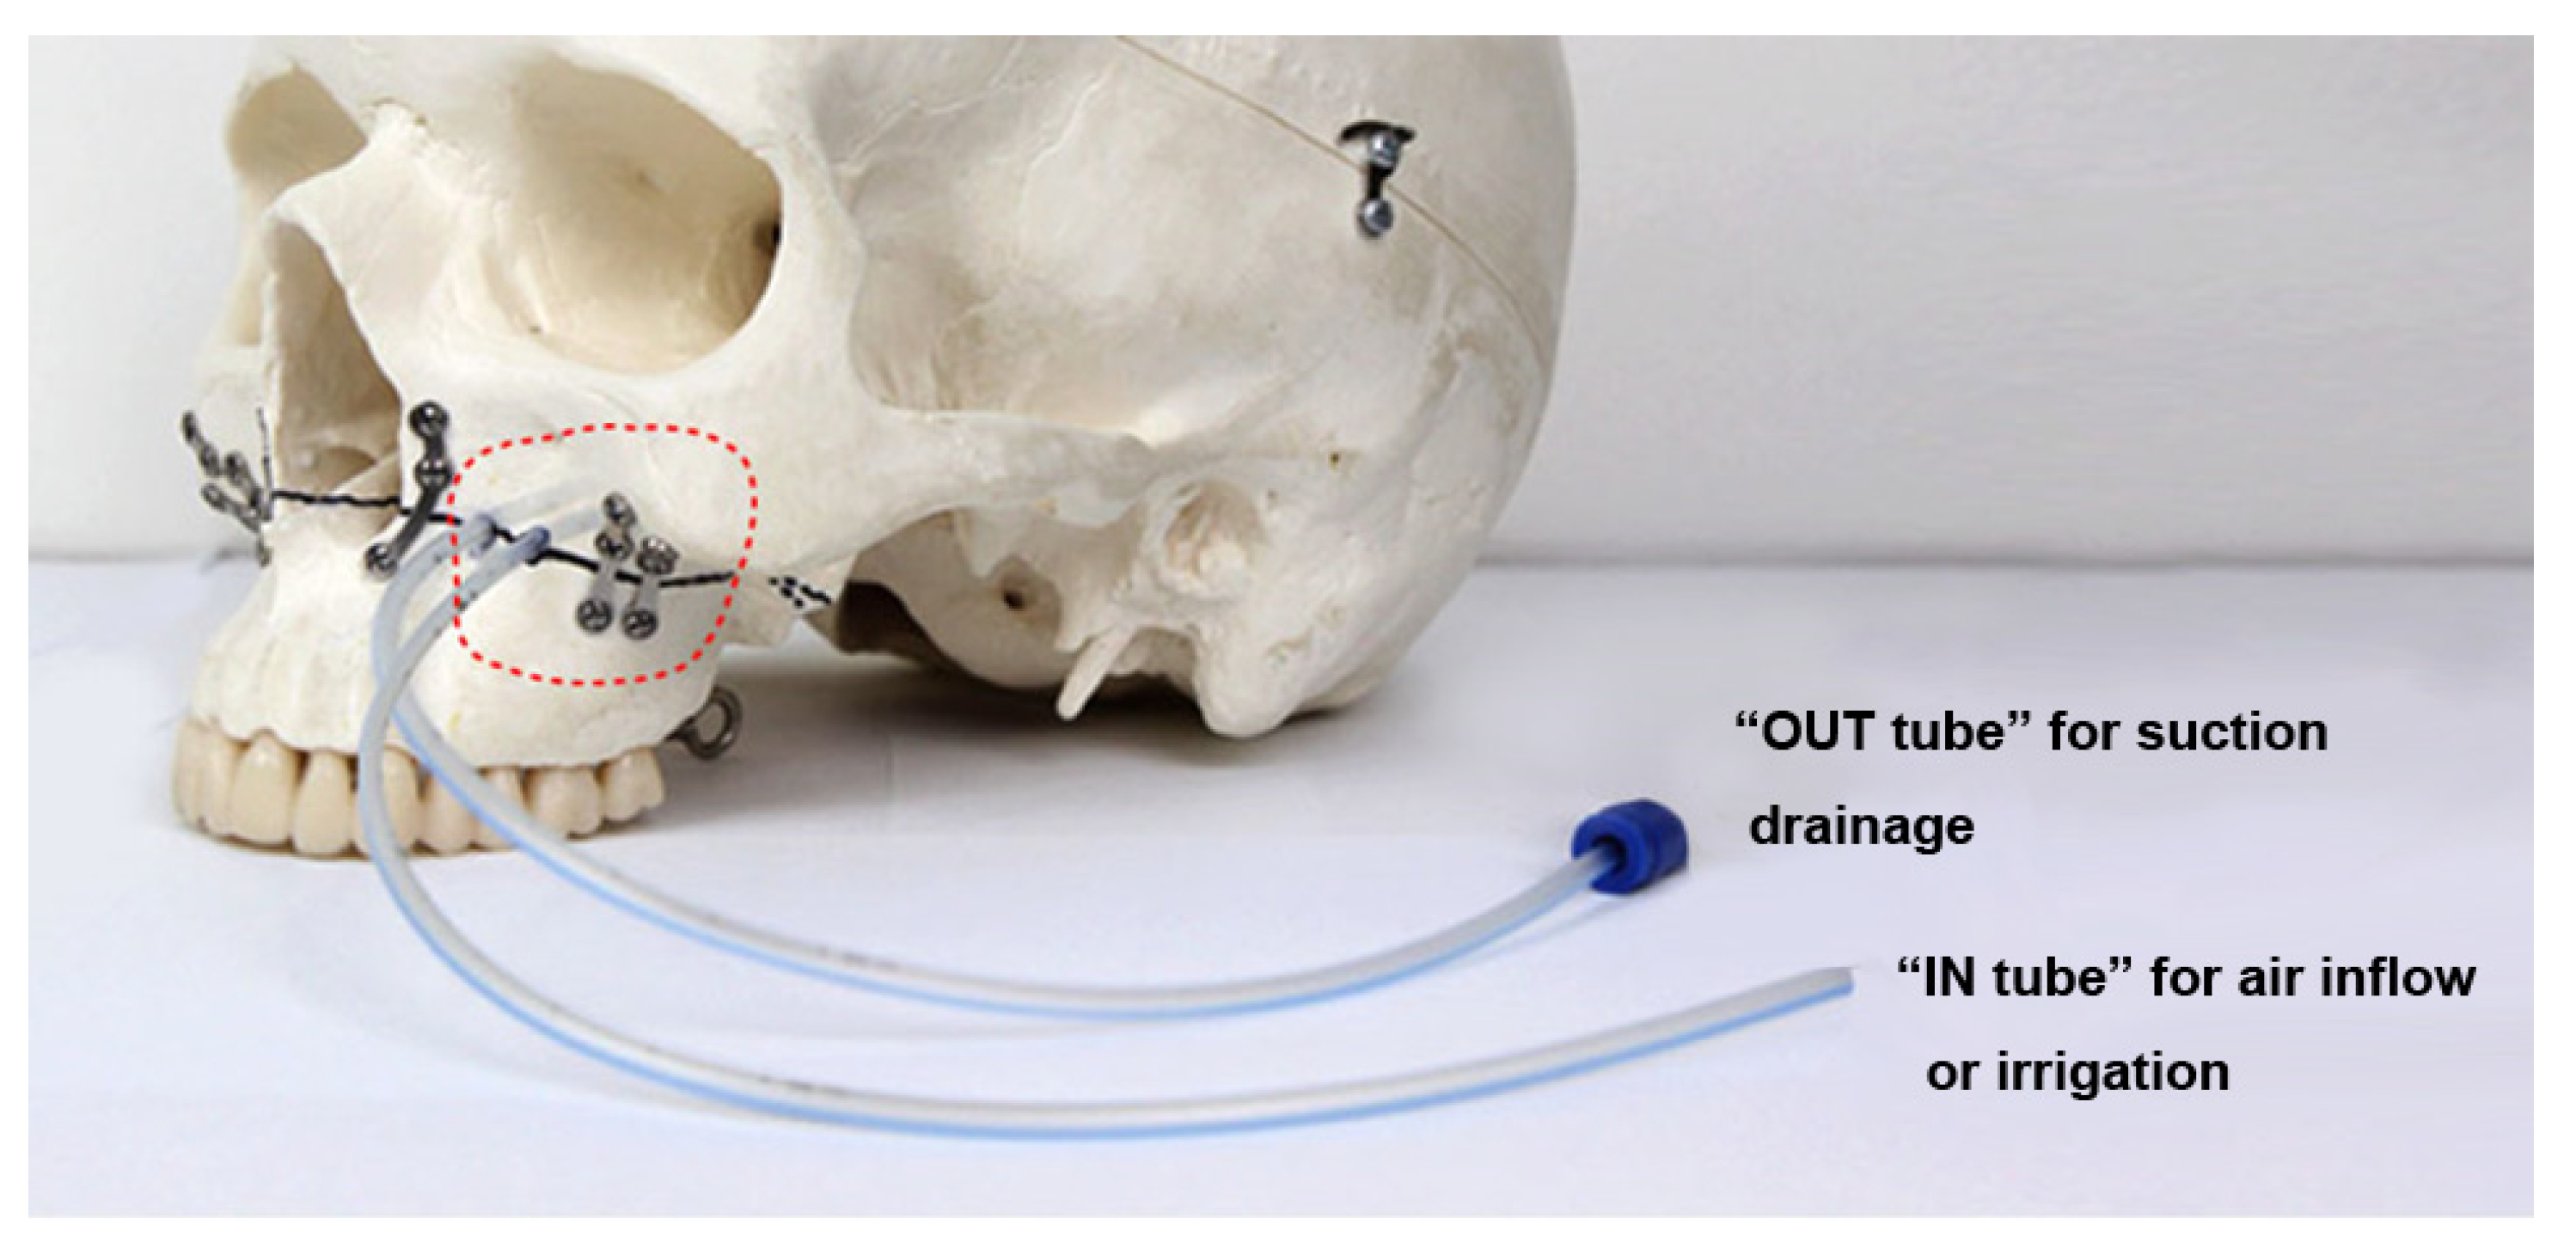

2. Materials and Methods